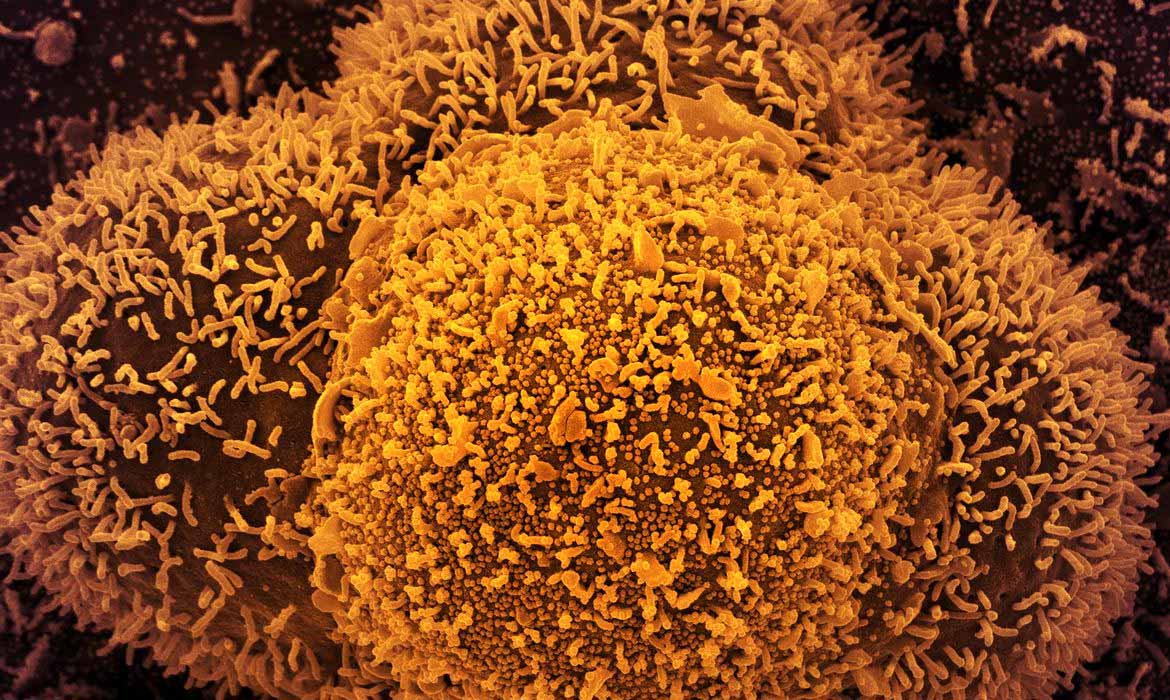

Foi identificado o caso de mais uma variante do novo coronavírus no Brasil. O Instituto Butantan informou que encontrou uma pessoa infectada com a subvariante denominada XE, que mistura duas modalidades da Ômicron.![]()

A variante XE é uma combinação de duas cepas diferentes da Ômicron: BA.1 e BA.2. O primeiro caso foi mapeado na cidade de Londres, em janeiro deste ano. Segundo o Instituto Butantan, a taxa de crescimento da XE é 10% superior à da cepa BA.2.

Contudo, o Instituto informa que ainda não há evidências suficientes acerca de mudanças, vantagens e desvantagens da circulação a nova variante em aspectos como gravidade, transmissão e eficácia de vacinas já existentes.